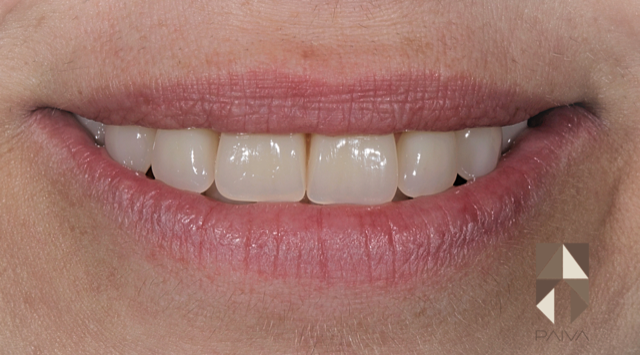

Actualités Réhabilitation totale maxillaire sur implants : un cas clinique

Face à ce plan de traitement, nous avons décidé de procéder à l’implantation de 6 implants concomitante aux extractions dentaires, suivi de la pose immédiate d’une prothèse fixe sur les implants.

En un seul rendez-vous l’esthétique et la fonction ont été restaurées.